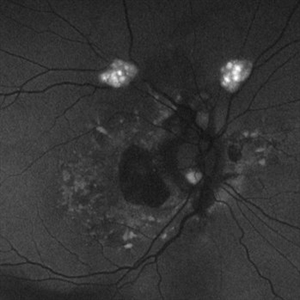

Astrocytic Hamartoma

Feb 27 2025 by Daniel Davis, OCT-C

Fundus autofluorescence photo of 55-year-old female with astrocytic hamartoma in association with tuberous sclerosis. No treatment options available, benign. Other findings include; Posterior Vitreous Detachment, Vitreous Hemorrhage, Hereditary Retinal Dystrophy, Vitreous Opacities, Hypertensive Retinopathy.

Photographer: Daniel Davis, OCT-C

Imaging device: Optos California

Condition/keywords: astrocytic hamartoma, fundus autofluorescence (FAF)